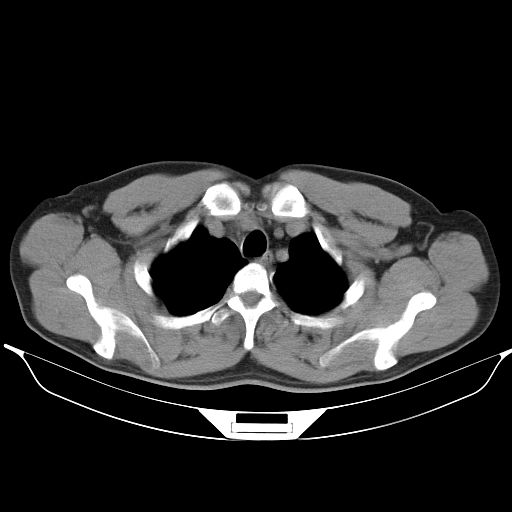

标题: CT25490:男,40岁,体检发现;无其它不适。 [打印本页]

标题: CT25490:男,40岁,体检发现;无其它不适。

考虑右下肺周围性肺癌并肺内多发转移,纵隔淋巴结转移!

支持 !考虑右下肺周围性肺癌并肺内多发转移,纵隔淋巴结转移,(气管前腔静脉后,隆突下,主动脉弓下都有了)

考虑肺霉菌病。